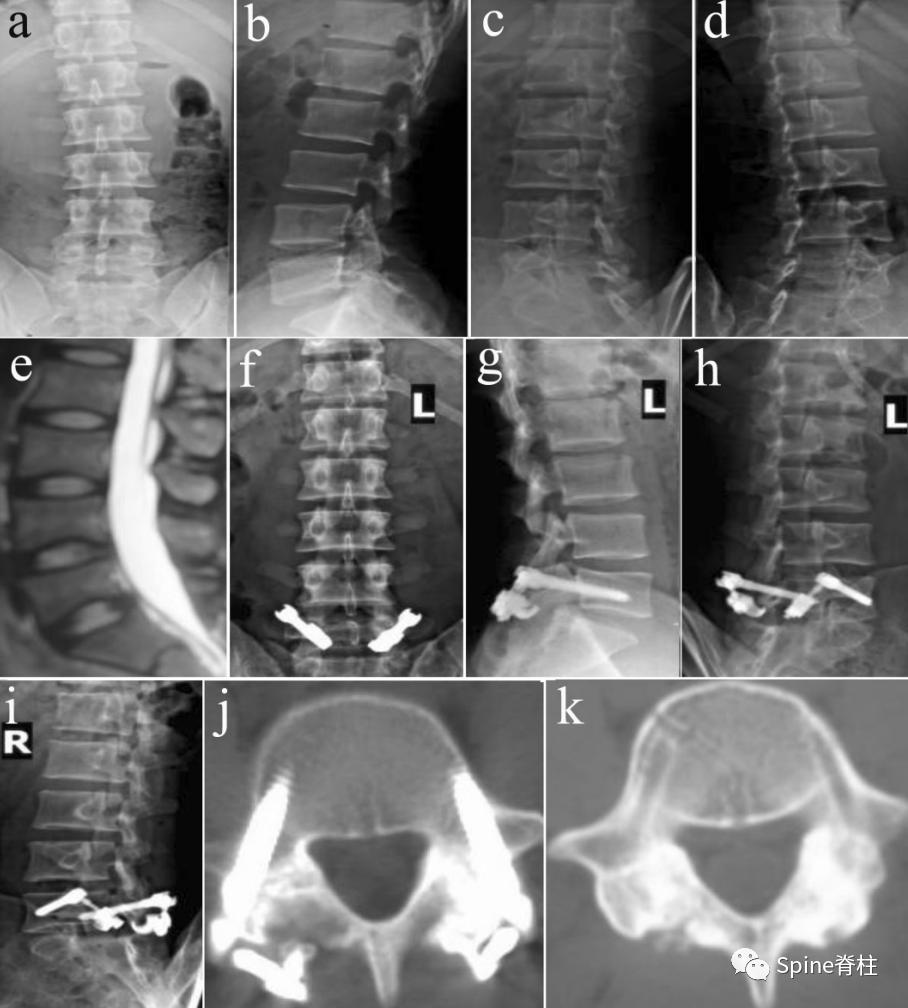

1. 峡部裂的Morita分型

- 早期 (early):可见峡部骨折线

- 进展期 (progressive):骨折断端间隙增宽

- 终末期 (terminal): 假关节形成

图:早期(a),进展期(b),终末期(c)

随后,Sairyo教授进一步CT研究,将Morita分型早期又分为 最早期 (very early): 骨折线模糊或不连续的骨折线和 晚早期 (late-early): 骨折线清晰明显。

图:腰5双侧峡部裂,右侧为 最早期 ,左侧为 晚早期